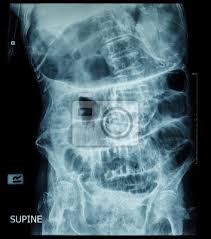

Der ileus ( latinisierte form des griechischen εἰλεός ileós, von altgriechisch εἰλεῖνeilein, deutsch ‚einschließen, zusammendrängen' ), deutsch darmverschluss, ist eine unterbrechung der darmpassage. Bei bedarf erhalten sie dabei das passende rezept oder eine krankschreibung direkt aufs handy. Bei einem darmverschluss handelt es sich um eine blockierung, bei der der darminhalt überhaupt nicht mehr oder nur bedingt weiterbefördert wird. Erbrechen von mageninhalt, später können die betroffenen auch bräunlichen darminhalt oder sogar kot erbrechen. Beim darmverschluss ist eine operation meist unumgänglich. Die vorstufe des ileus wird subileus genannt. Ein akuter verschluss des darms stellt immer einen notfall dar und muss umgehend behandelt werden, da er sonst lebensgefährlich ist. Auch zu e inem darmverschluss (ile us) kommen.